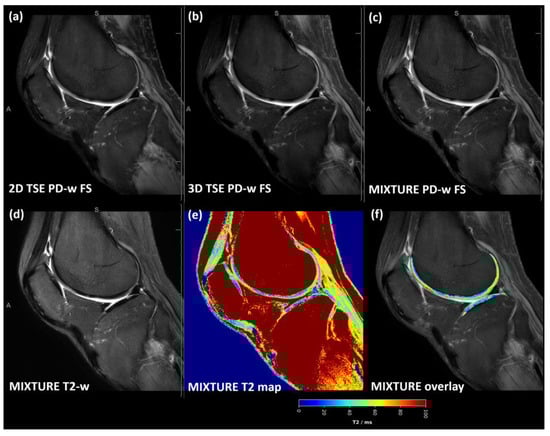

3.2. Two-Dimensional TSE PD-Weighted FS Images Showed Most Pronounced Cartilage–Synovia Contrast

Across the acquired sequences, cartilage demonstrated an intermediate signal intensity and a layered zonal structure (Figure 2 and Figure S1). However, the ROI-based analysis yielded a significantly more pronounced contrast as evidenced by significantly more negative Weber contrast values between cartilage and synovia for the 2D TSE images (p < 0.001 [Figure 3a]). In visual terms, the negative Weber contrast values translate into a darker presentation of the cartilage tissue than the bright synovial fluid. Similarly, CNR values tended to be higher in the 2D TSE images, though not significantly (Figure 3b), and CV values were largely similar (Figure 3c).

Figure 2. For a representative slice (through the central lateral femorotibial compartment) and joint, the 2D TSE image (a), the 3D TSE image (b), and the MIXTURE image (c) are shown alongside the MIXTURE T2-weighted image (d), the MIXTURE T2 map (e), and the segmented cartilage tissue overlay (f). In this example, the segmented femoral and tibial cartilage exhibited T2 relaxation times of 48 ± 18 ms and 36 ± 16 ms, respectively (mean ± standard deviation). In areas of fatty tissue, the MIXTURE T2 map did not yield meaningful values because SPAIR fat saturation was employed during the acquisition of the PD-weighted FS morphologic images. Abbreviations: PD—proton density, -w—weighted, FS—fat-saturated, MIXTURE—Multi-Interleaved X-prepared Turbo Spin-Echo with IntUitive Relaxometry, SPAIR—Spectral Attenuated Inversion Recovery. Figure S1 provides a close-up of the femoral and tibial cartilage of the weight-bearing region.